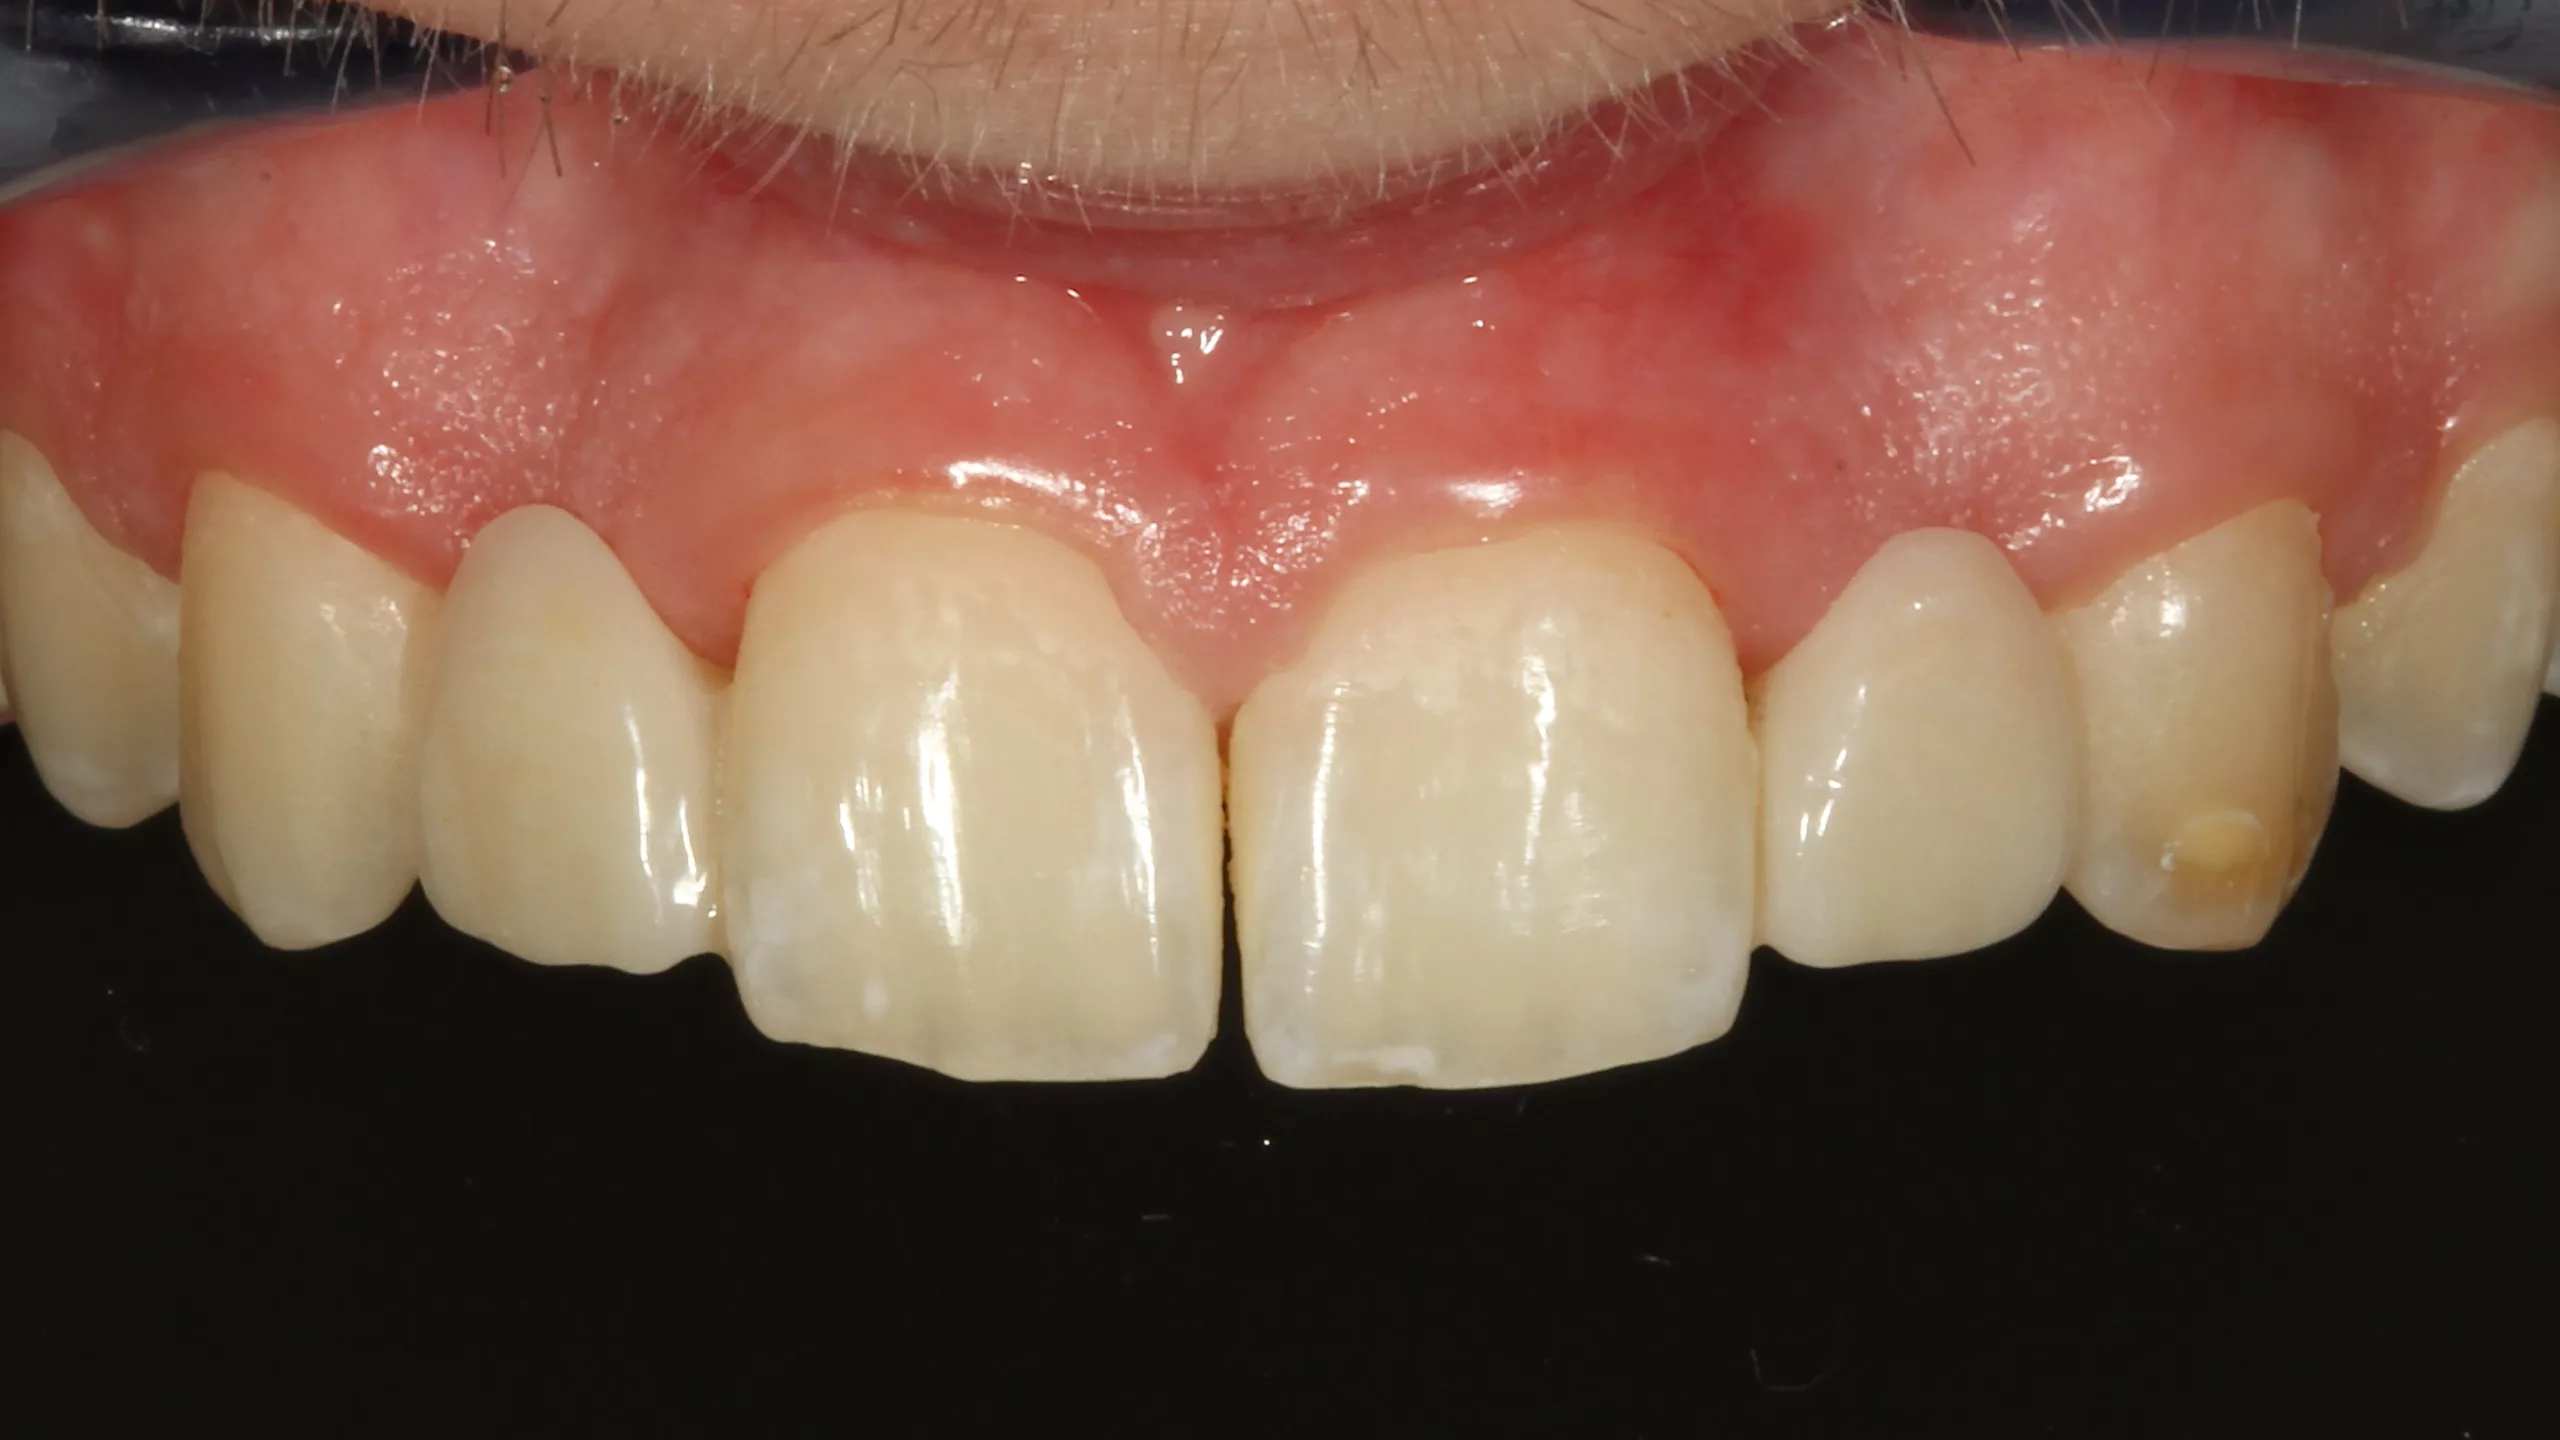

Die Abbildungen 35 und 36 zeigen die eingesetzte Arbeit und das zufriedene neue Lächeln der Patientin. Leider konnte im vorliegenden Fall die äußerst dunkle Farbe des Zahnstumpfes von Zahn 22 nicht komplett kaschiert werden. Die Verwendung einer bei Visalys Cem-Core ebenfalls zu Verfügung stehenden, sehr opaken Variante des Materials wurde kurzzeitig erwogen, dann allerdings wiederum verworfen, weil die doch sehr hohe Opazität die Gesamtästhetik vielleicht eher negativ beeinträchtigen könnte. Ein Beispiel zur Verwendung dieses opaken Befestigungs- und Aufbaumaterials zeigt später der letzte Fall dieses Beitrags.